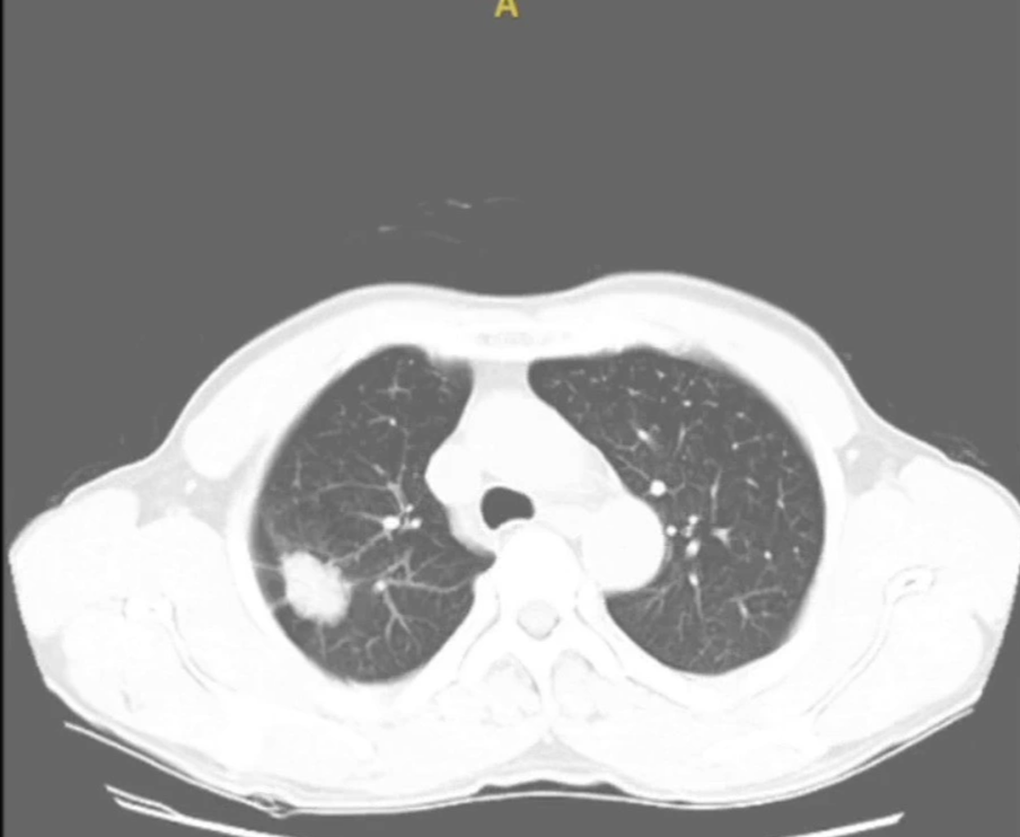

Hình ảnh khối u ác tính trên phổi người bệnh (Ảnh: Bệnh viện K).

Kết quả chụp cắt lớp vi tính cho thấy bệnh nhân có khối u thùy trên phổi phải kích thước khoảng 2,5cm với tính chất hình ảnh điển hình của khối u ác tính. Đánh giá toàn thân bệnh nhân không có di căn, chức năng phổi và tim mạch ở mức bình thường. Bệnh nhân được chẩn đoán ung thư thùy trên phổi phải, giai đoạn I (T1N0M0).